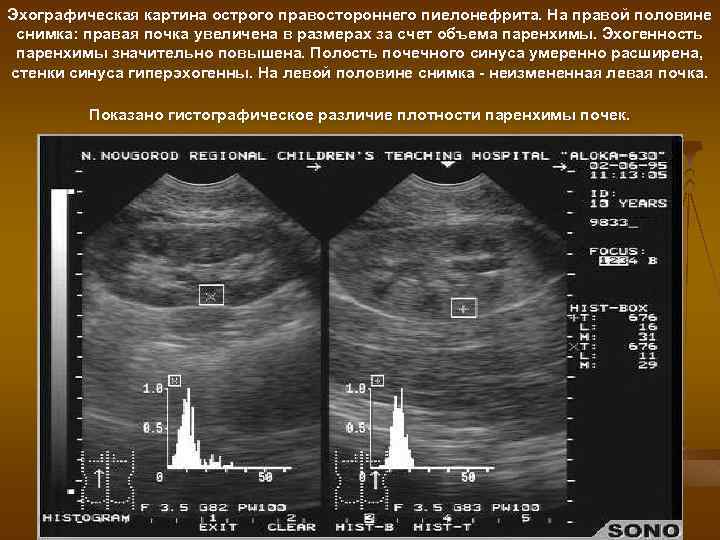

Эхографическая картина острого правостороннего пиелонефрита. На правой половине снимка: правая почка увеличена в размерах за счет объема паренхимы. Эхогенность паренхимы значительно повышена. Полость почечного синуса умеренно расширена, стенки синуса гиперэхогенны. На левой половине снимка - неизмененная левая почка. Показано гистографическое различие плотности паренхимы почек.